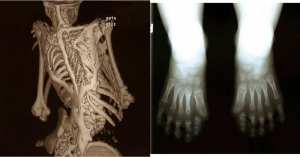

• كثرة الأصابع

كثرة الأصابع

عيب خلقي يكون عبارة عن أصابع قدم إضافية أو أصابع يد إضافية، طفل من كل 500 طفل يكون مصابا بهذا المرض، لا يوجد علاج لهذا العيب الخلقي إلا الجراحة لاستئصال ...